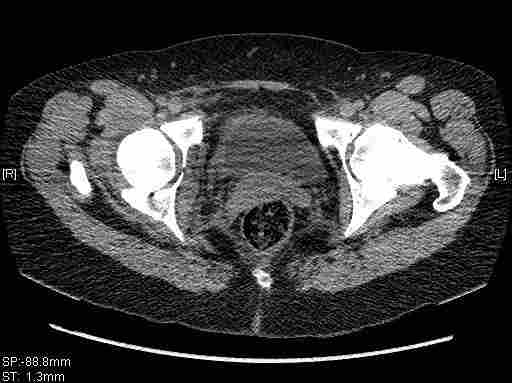

Женщина,58 лет, после ДТП 6 суток. Первично повреждение расценено как переломы ветвей лонной кости. После подтверждения повреждения вертлужной впадины,как чаще всего случается, вопрос встал о тактике. БОльшинство за консерватиное лечение.К сожалению кт у нас "во время" сломался. Прилагаю стандартные снимки вертлужки. У меня следующие вопросы к коллегам:1. Правильно ли рассценивать это повреждение как Т-образный перелом вертлужнй впадины?2. Можно ли добиться анатомической репозиции поверхности вертлужной впадины скелетным вытяжением в данном случае, если нет, что будет этому препятствовать?3. Если смещение останется таким как сейчас, через какое время появится необходимость эндопротезирования (по вашему опыту)?Спасибо.

Удалось сегодня вывести пациентку в соседнюю больницу, где есть кт. Срезы сделаны только горизонтальные.

|